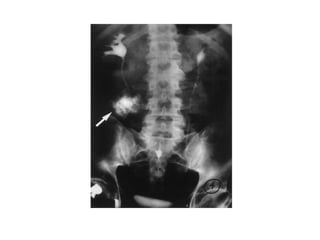

The kidneys can be injured by blunt or penetrating trauma, requiring timely medical evaluation. The kidneys are normally protected by back muscles but can be damaged by severe impacts or objects piercing the skin. Blunt trauma may cause bruising while penetrating injuries like gunshots can enter elsewhere and travel to the kidneys. Most kidney injuries are minor but evaluation with imaging tests like ultrasound or CT scans helps classify the injury and guide management, which may include rest, antibiotics, surgery, or nephrectomy in more severe cases.